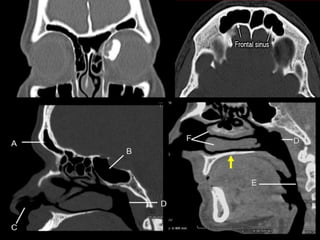

• #4 The frontal sinus provides the convex contour of the frontal bar. It is thickened & gives structure to the supraciliary & glabellar areas. It is an epithelial lined cavity

• #6 The olfactory bulbs are & tracts are in close contact to the cribriform plate, & the dura is tightly adherent to the to bone in the olfactory groove.Underlying the cribriform plate is the olfactory mucosa of the upper nasal cavity

• #7 Also we note of the SINUS DRAINAGE or the the Nasofrontal duct which is not a correct term. We know that it is large enough to maintain drainage function during the acute phase of trauma.There is no true tubular connection between the frontal sinus and the nose exists; it is most often a relatively large opening, directly into the frontal recess of the nose or anterior ethmoid.the frontal recess may take the appearance of a duct when narrowed by theethmoid bulla or a pneumatized agger nasi cell.Laryngoscope. 2001 Apr;111(4 Pt 1):603-8.Surgicalanatomy of the nasofrontalduct: anatomical and computedtomographicanalysis.Kim KS, Kim HU, Chung IH, Lee JG, Park IY, Yoon JHAbstractOBJECTIVES:Although complete anatomicalknowledge of the nasofrontalducthasbeen of greatimportance, littleisknownaboutit. The aim of thisstudyis to examine the drainage site of the nasofrontalduct and to investigate the anatomicalboundaries of the nasofrontalductaccording to the drainage site.STUDY DESIGN:Onehundredsagittallydividedadult head specimenswereanalyzed by computedtomography and dissection under the surgicalmicroscope.METHODS:Computedtomographyscans of 50 adultcadaver heads weretakensagittallyat 1-mm intervals and coronallyat 3-mm intervals to find the nasofrontalduct. Onehundredspecimens, made up of sagittallydividedadultcadaver heads, weredissected under the microscope to study the structure of the nasofrontalduct.RESULTS:Weidentified the anterior, posterior, medial, and lateralboundaries of the nasofrontalduct. In the most common type, the superiorportion of the uncinate processformed the anteriorborder and the superiorportion of the bulla ethmoidalisformed the posteriorborder of the nasofrontalduct. The conchalplateformed the medialborder and the suprainfundibularplateformed the lateralborder of the nasofrontalduct. Othervariations are described in detail.CONCLUSIONS:To widen the nasofrontalcommunication, removing the upperportion of the ground lamella of the ethmoid bulla, whichis the posteriorboundary of the nasofrontalduct, with cuttingforcepsseems to be a safe and easy method.

• #8 FRONTAL SINUS fracture is defined as fractures involving one or more sinus wall fracture however,

• #9 FRONTOBASILAR Fractures are fracture extending into or beyond the ethmoid sinuses & cribriform plate which is a distinct & completely different & more complex injury.

• #13 Thin section axial, coronal or sagittal CT are required for accurate documentation of frontal sinus fractures. However, CT scans may only suggest direct evidence of potential outflow tract obstruction that could lead to infections because of the presence of the ethmoid cells surrounding the drainage opening.